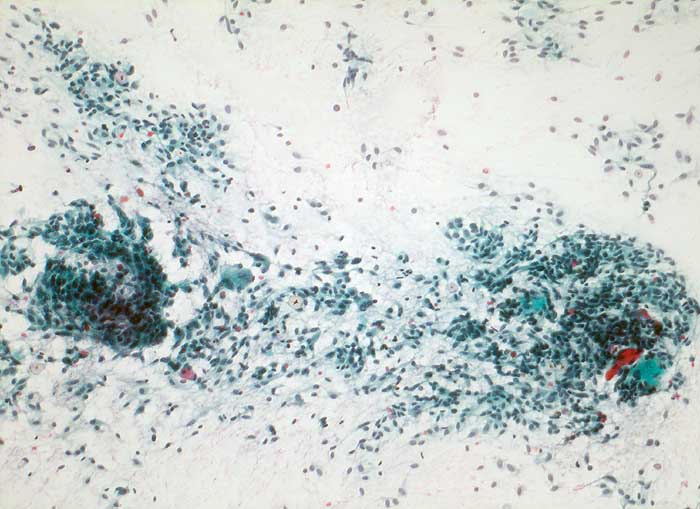

Medulläres Schilddrüsenkarzinom

Die Tumorzellen sind polygonal bis spindelförmig. Die gleichförmigen Kerne liegen exzentrisch im zyanophilen Zytoplasma. Das Zellbild kann ausgesprochen monomorph imponieren. Das Kernchromatin ist fein granulär und wenig atypisch. Die Nukleolen sind meist unscheinbar. Gelegentlich finden sich Kernvakuolen. In einigen Fällen ist Amyloid in Form einer homogenen zyanophilen bis leicht eosinophilen Masse nachweisbar. Es ist weniger stark angefärbt als Kolloid. Amyloid kann mit Hilfe einer Kongorotfärbung am vorher nach Papanicolaou gefärbten Präparat dargestellt werden. Aufgrund der unterschiedlichen Morphologie können medulläre Karzinome mit zahlreichen anderen Tumoren verwechselt werden (oxyphile Tumoren, follikuläre und papilläre Schilddrüsenkarzinome, anaplastisches Karzinom, Fibrosarkom). Medulläre Karzinome exprimieren im Gegensatz zum Schilddrüsenkarzinom Calcitonin und CEA, aber kein Thyreoglobulin.